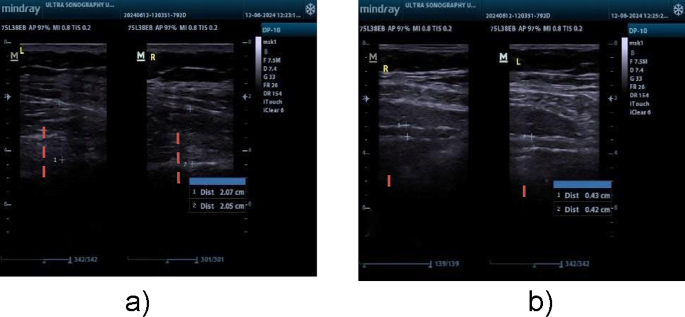

Ultrasonography is a dependable and valid technique with strong intrarater reliability for assessing transverse abdominis and lumbar multifidus muscle thickness in patients with chronic low back pain (CLBP). All measurements of muscle thickness in this research were conducted by one operator, guaranteeing strong interrater reliability. Research has consistently demonstrated elevated ICCs for thickness assessments and contraction ratios in the transversus abdominis and lumbar multifidus muscles under both static (ICC = 0.71–0.99) and semidynamic conditions (ICC = 0.73–0.98)20. Ultrasonography was utilized to assess the LM and TrA muscles. Mindray DP10 ultrasonography was used. For the LM muscle, participants were positioned face down with a cushion under the abdomen to reduce lumbar lordosis. The thickness was measured between the fascial plane separating the muscle from the subcutaneous tissue and the posterior aspect of the L4-5 facet joint21 (Fig. 2a).

r the TrA muscle, a linear ultrasonic transducer was placed horizontally on the abdominal wall at the midpoint between the iliac crest and the lower edge of the rib cage, with its inner edge approximately 10 cm from the midline. The individual was positioned comfortably on their back, with a cushion positioned beneath the knees. The probe was placed with its inner edge approximately 10 cm away from the midline. The probe’s ultimate placement was adjusted to guarantee that the medial edge of the transversus abdominis (TrA) was approximately 2 cm away from the medial edge of the ultrasound image while the participant was in a relaxed position21 (Fig. 2b).